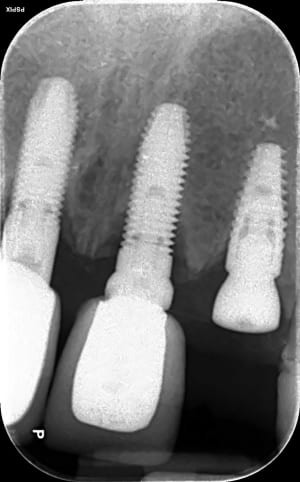

20-04-2021 Panoramique Début.JPG

10-07-2025 Panoramique Fin.JPG